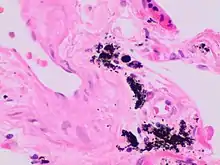

Micrograph of the spleen showing darkly stained, spheroid Gamna-Gandy bodies (arrows) outside the vessel wall at the center. Also shown is diffusely scattered, brown, granular hemosiderin pigment (arrowheads), indicating previous hemorrhage (hematoxylin & eosin staining, 40x magnification).